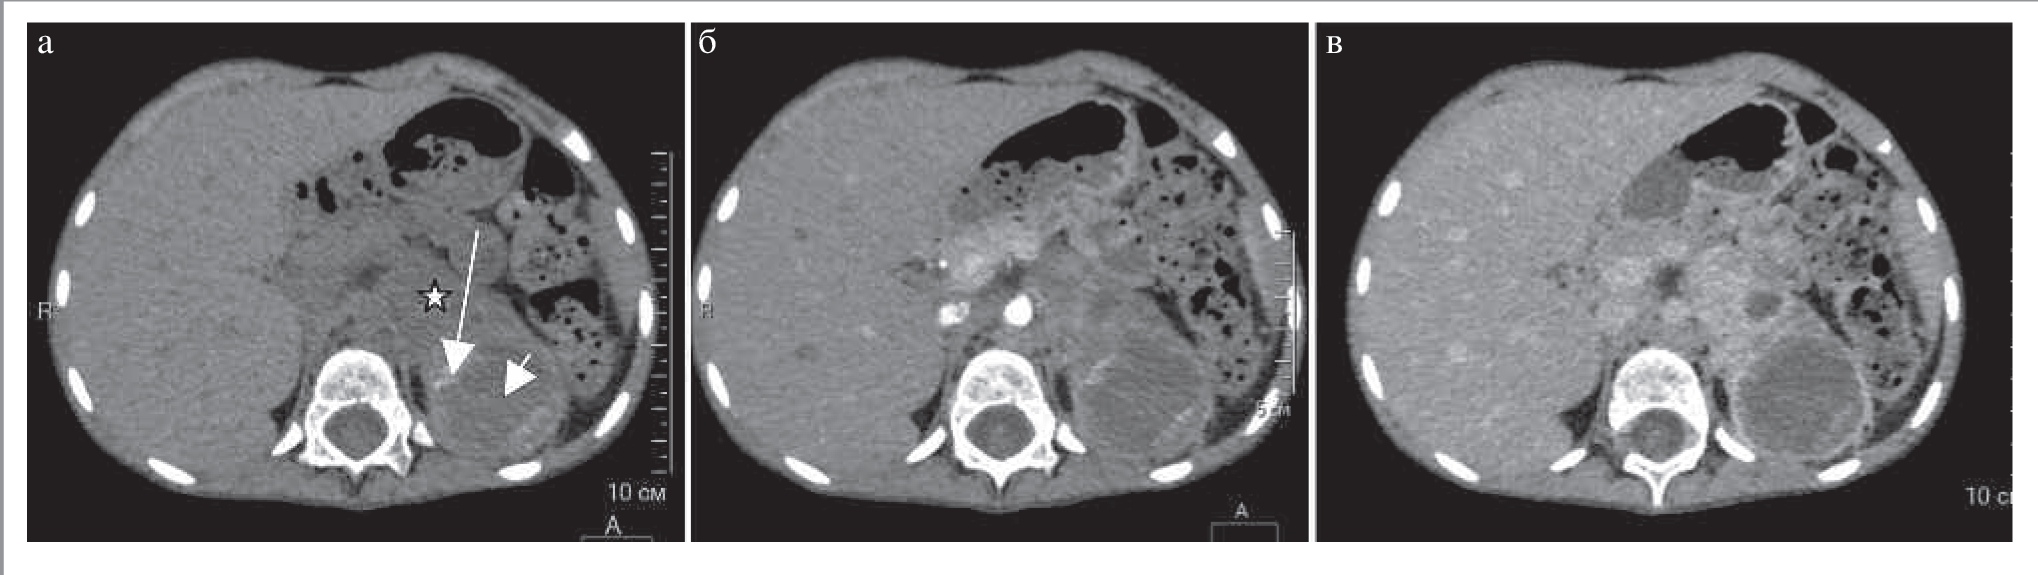

Нейробластомы представляют собой крупные образования неоднородной структуры, чаще поражающие надпочечники, но так же, как и феохромоцитомы, могут быть обнаружены в любом другом месте вдоль симпатического ствола [12]. КТ-картина сходна с АКР и лимфомой (рис. 10). Для нейробластомы характерен выраженный инвазивный рост. Наиболее часто метастазы этой опухоли обнаруживают в печени и костях. Основным заболеванием, с которым следует дифференцировать нейробластому, является нефробластома (опухоль Вильмса). Для нейробластомы характерны наличие кальцинатов, охватывание сосудов без их инвазии, возраст пациентов до 2 лет, нечеткие, неровные контуры и распространение образования в контрлатеральную сторону за пределы срединной линии. Опухоль Вильмса, наоборот, характерна для детей более старшего возраста (3–4 года), имеет более четкие, ровные контуры. Для нее характерны смещение и инвазия сосудов (например, нижней полой вены).

Рис. 10. МСКТ, аксиальная проекция. Нейробластома левого надпочечника. КТ-изображения в аксиальной проекции: а – НФ; б – АФ; в – ВФ. В левом надпочечнике определяется неправильной формы образование с зонами обызвествлений (длинная стрелка) и участками некроза (короткая стрелка). Солидный компонент (звезда) умеренно накапливает контрастный препарат. (Изображения представлены с любезного разрешения д.м.н., проф. А.В. Горбунова и Д.Г. Коваленко, ГБУЗ «Морозовская детская городская клиническая больница» Департамента здравоохранения г. Москвы.)